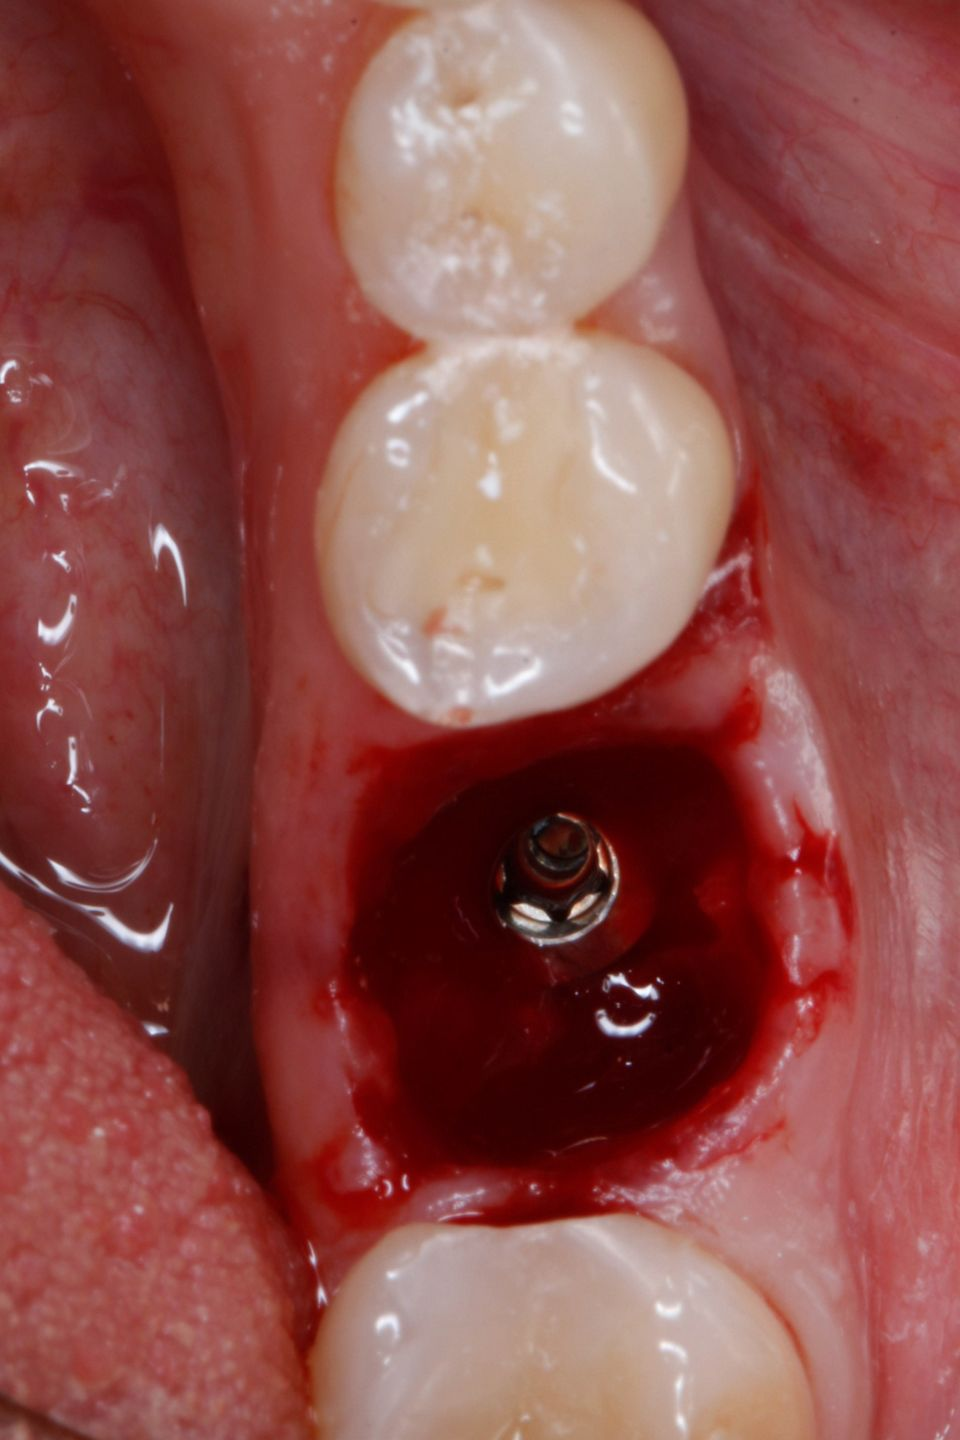

#36 牙的手术过程从局部麻醉和下牙槽神经阻滞开始。通过分割磨牙根实现无翻瓣反射的无创拔牙;从而保留肺泡壁和根间隔膜(图3-4)。仔细清洁牙槽,形成种植体路径并放置Straumann ® BLX 种植体 5.5 x 8 mm (图 5-7)。为了促进非浸没式愈合,将标准愈合基台连接至种植体。骨壁和种植体之间的间隙填充有同种异体骨材料颗粒(maxgraft®,botiss 生物材料,德国)。应用富含血小板的纤维蛋白(PRF)来实现适当的初步愈合。调整软组织边缘并用聚丙烯 6/0 缝合,使愈合基台暴露(图 8-9)。将粘性牙周Reso-Pac ®敷料(来自德国杜伊斯堡的Hager & Werken)放置在治疗区域上以协助愈合过程(图10)。